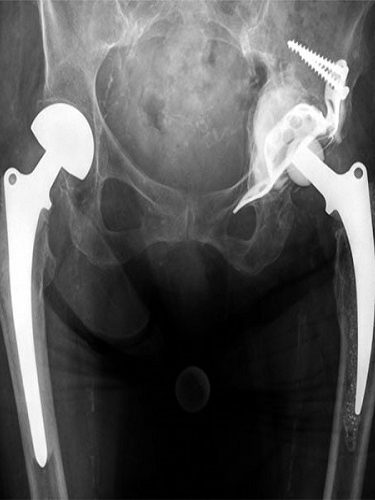

– OVER KİST AMELİYATI (YUMURTALIK KİSTİ AMELİYATI) (OVER KİSTEKTOMİ) Hemen her kadında hayatını belirli bir döneminde over kistlere rastlanabilmektedir. Bu kistlerin farklı tüpleri bulunmaktadır. Bu çeşitliliğe uygun tedavi yöntemleri de bulunmaktadır. Over kistlerinde en sık rastlanan şikayetler cinsel ilişki sırasında ağrı, kasık ağrısı, karında şişkinlik veya basınç hissi ve adet düzensizlikleridir. Yumurtalık (over) kistleri her…